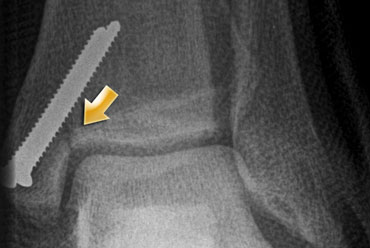

On the left a 25-year old professional soccer player with complaints of the ankle.

Evident marrow abnormalities on coronal STIR sequence MRI was seen, but there was doubt about the presence of a fracture line.

At 11 months follow-up a clear fracture line is visualized by CT.

Post operative radiograph Post operative radiograph

On the left the postoperative radiograph with screws and lower leg cast at 12 months.

It shows a just discernable fracture line at the typical location: the junction of the tibial plafond and inner vertical line of the medial malleolus